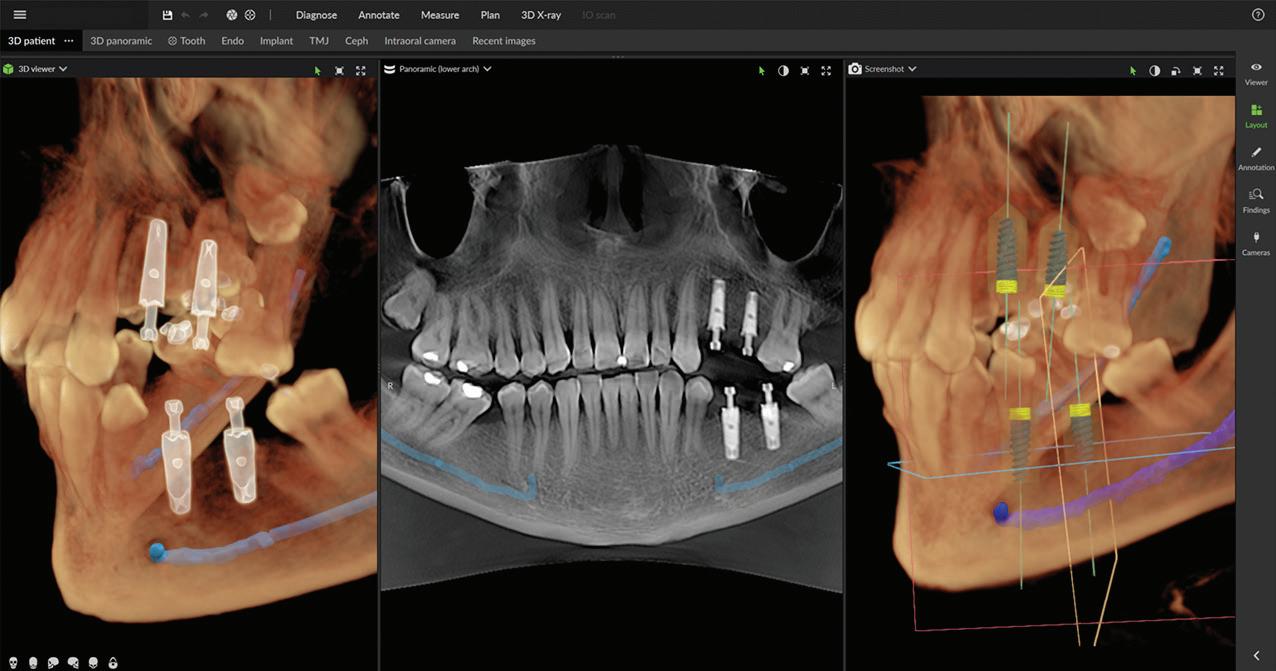

Seamless integration with new DTX Studio™ Clinic software

P acked with AI-assisted software features, DTX Studio™ Clinic complements OP 3D LX in numerous ways—for example, correcting patient positioning errors and detecting

Figure 4. Maxillofacial surgery. Figure 6. TMJ analysis. Figure 8. Airway analysis. Figure 10. Periodontics. Figure 5. Orthodontics. Figure 7. Implant placement. Figure 9. Prosthodontics. Figure 11. Endodontics.

landmarks, annotating mandibular nerve canals, tracing patientspecific panoramic curves for mandible and maxilla and merging CBCT and intraoral scan data for improved implant planning. These intuitive award-winning software features support a more efficient workflow allowing you to spend less time in the software and more time with your patient.

Figure 12. Merge CBCT and intraoral scans. Figure 13.Automatic focal trough. Figure 14. Mandibular nerve canal annotation. * Optional field of view.